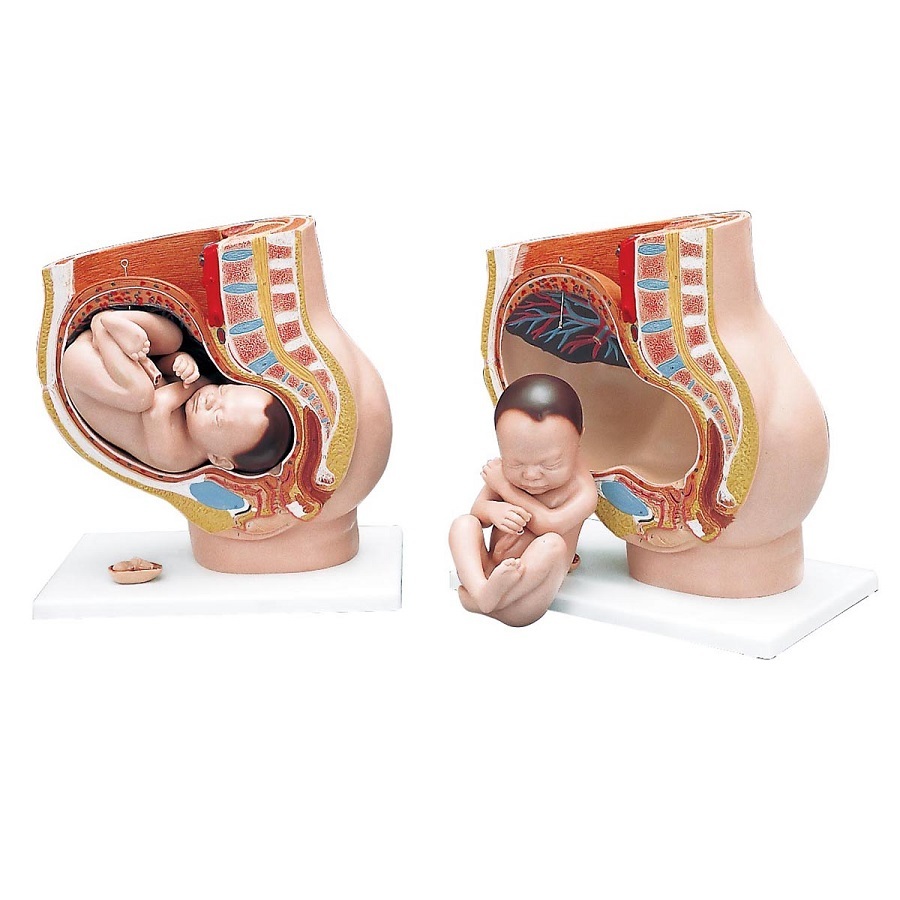

Физиология беременности: строение органов

Раздел: Моменты озарения